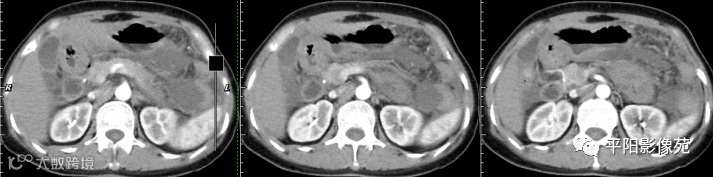

腹部增强 门脉期

壁腹膜增厚伴或不伴腹水;增厚的腹膜光滑、均匀,呈线带状,部分可见腹膜结节,网膜及肠系膜广泛浸润性改变;增强扫描明显强化。

合并淋巴结肿大,可钙化,若中心干酪样坏死,增强扫描环形强化

湿型:渗出性高密度腹水(CT值20-45HU),高密度由于高蛋白和细胞含量多可能。